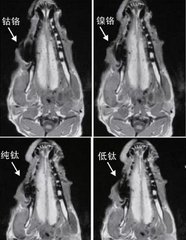

還有,如果拍攝核磁共振的部位距離口腔比較遠,通常影響也是比較小的,不用過於(yu) 擔心。但是影響還是有的。具體(ti) 的影響呈現在成像上,在相應的位置會(hui) 有較大的偽(wei) 影(也就是陰影部分),如果位置很近的話,可能會(hui) 影響醫生的判斷。

金屬烤瓷牙和全瓷牙內(nei) 層材料的**